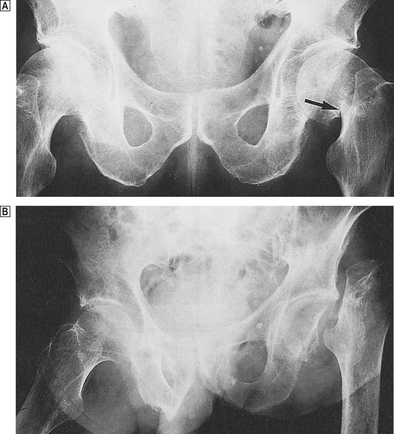

This usually presents with pain and limitation of joint movement. For anatomical reasons, fractures of bones such as the neck of the femur (Fig. 25.11) or the scaphoid deprive some areas of adjacent bone of their blood supply. Necrosis is then an inevitable consequence. Surgical treatment is therefore sometimes necessary to replace the fractured head of femur. The cause of other cases of avascular necrosis is less certain. Lesions occur in patients treated with corticosteroids, in sickle cell disease and other haemoglobinopathies. Similar lesions develop in divers and are probably the result of air embolism, associated with decompression.

image

Fig. 25.11 Fracture of femoral neck. image Compare the normal contours of the femoral neck on the right with the fracture on the left (arrowed). image There is a displaced fracture of the left femoral neck (detected 8 weeks after a fall!) resulting in necrosis of the bone deprived of its blood supply.